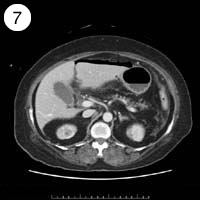

57歳 女性

単純CT

造影CT